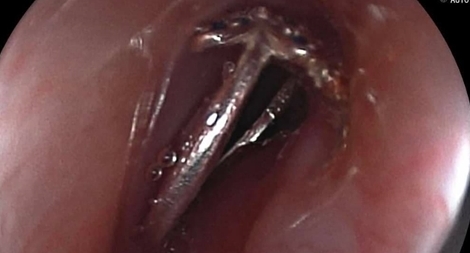

Nguồn tin từ Bệnh viện đa khoa tỉnh Khánh Hoà ngày 5-7 xác nhận, các bác sĩ Khoa ngoại chấn thương, chỉnh hình – bỏng ở cơ sở y tế này vừa phẫu thuật lấy “chiếc nhẫn” bulong sắt hình lục giác chèn ép sắp gây hoạt tử ngón tay một bà cụ sinh sống lang thang.